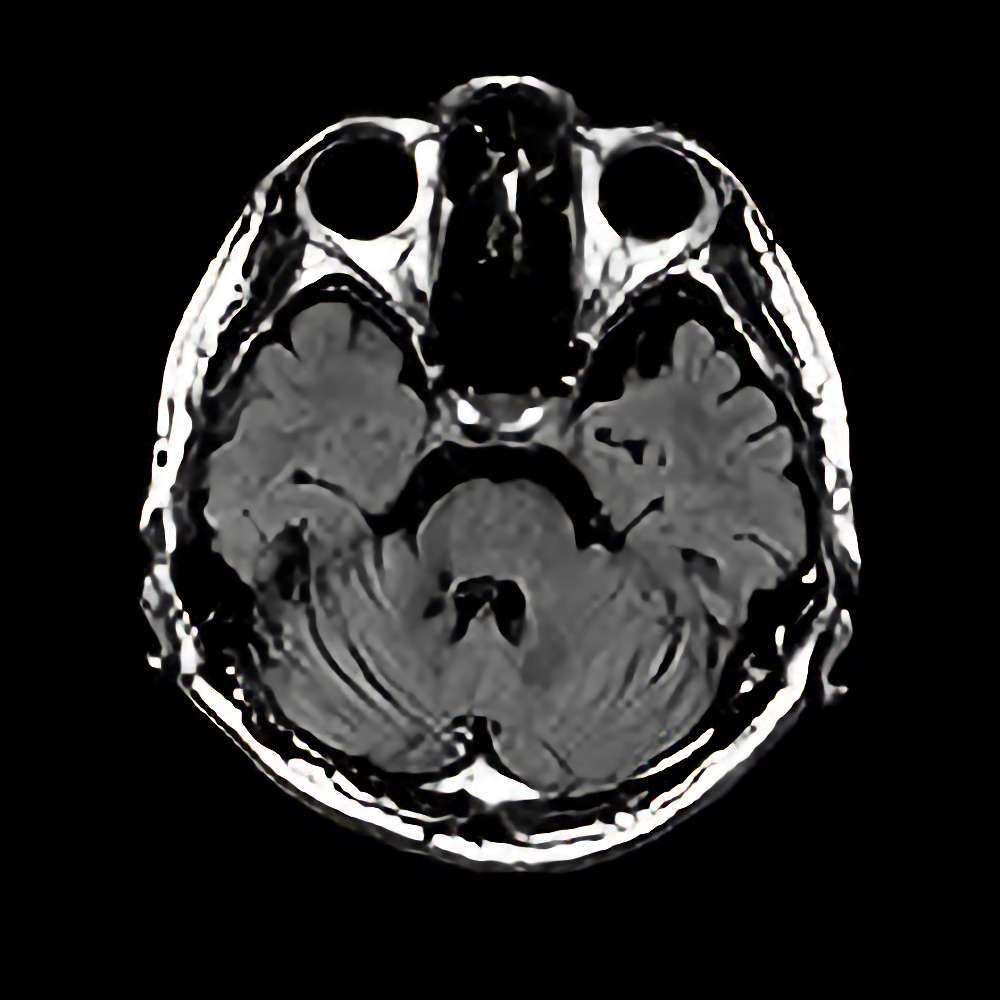

症例 '16年11月

No.

※ 画像をクリックすると拡大表示します。症例No.は平成29年から起算しています。

年_番号

手術年月

患者年齢

’16_164

'16年11月

30代

病名

術式

備考

海綿状血管腫

(右脳幹部)

断層撮影

手術前

1

手術前2

手術後